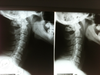

This relates to the moveable bones of the spine called vertebrae which get out of proper alignment and interfere with proper nervous system function.Β When this occurs the communication between the brain and the body becomes distorted and there is abnormal function as a result.